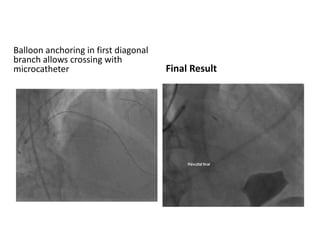

Balloon anchoring in first diagonal

branch allows crossing with

microcatheter Final Result

Balloon anchoring infirst diagonal branch allows crossing with microcatheter Final Result